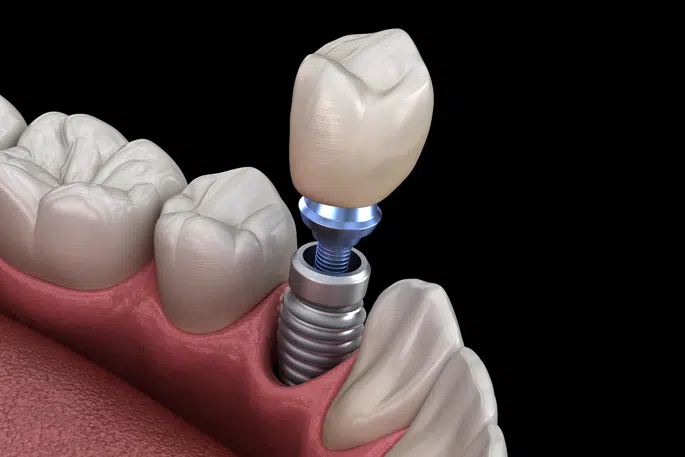

Dental implants are artificial tooth roots made of biocompatible titanium placed into the jawbone to replace missing teeth. They function like natural teeth and provide a strong foundation for crowns or bridges.